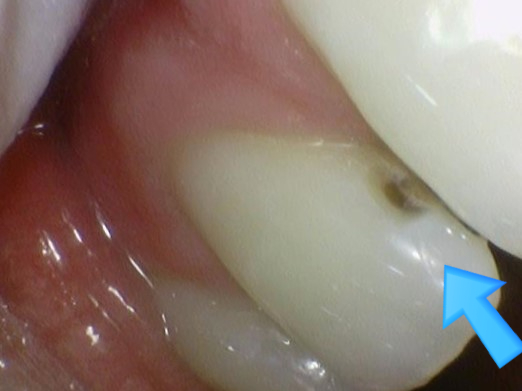

↑치료 전 사진.

↑치료 중간 환자분께 충치를 보여드리기 위해 찍은 사진